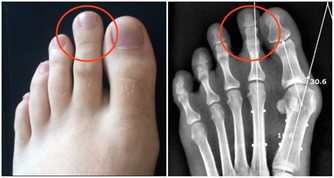

過度勞累會對您的身心健康產生深遠的負面影響。無論是背痛,沮喪,心臟問題,肥胖症,還是經常生病,都要考慮工作是否是原因。您會知道過度勞累何時會影響您的健康,並且您將不得不決定是否值得這樣做。